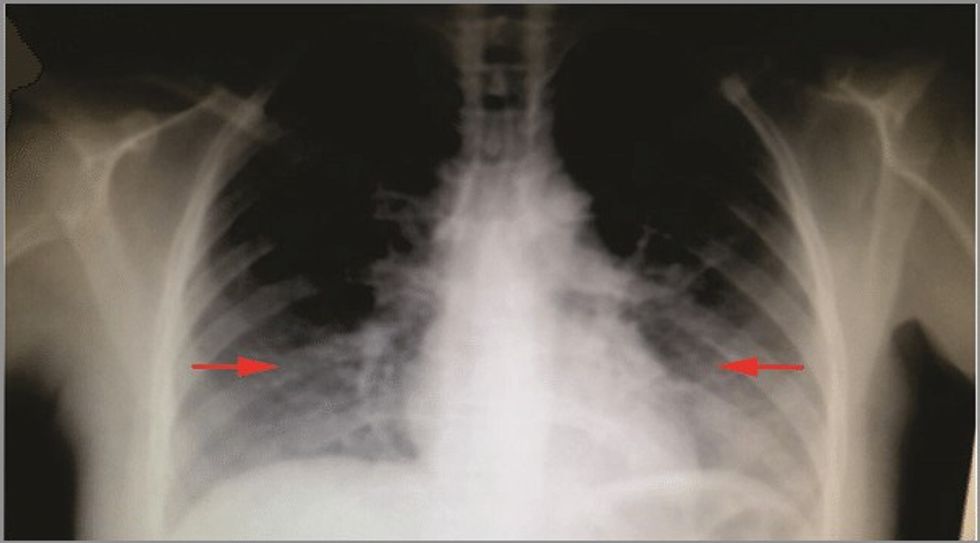

Pneumonia bilaterale intersticiale është një infeksion serioz që mund të shkaktojë inflamacion dhe cikatrizime në mushkëri.

Është një nga format e shumta të sëmundjeve intersticiale të mushkërive që përfshin indin përreth qeskave të vogla të ajrit (alveole) të mushkërive tuaja.

Këtë lloj pneumonie mund ta zhvilloni si pasojë e COVID-19. Format bilaterale të pneumonisë i përfshijnë të dy mushkëritë.